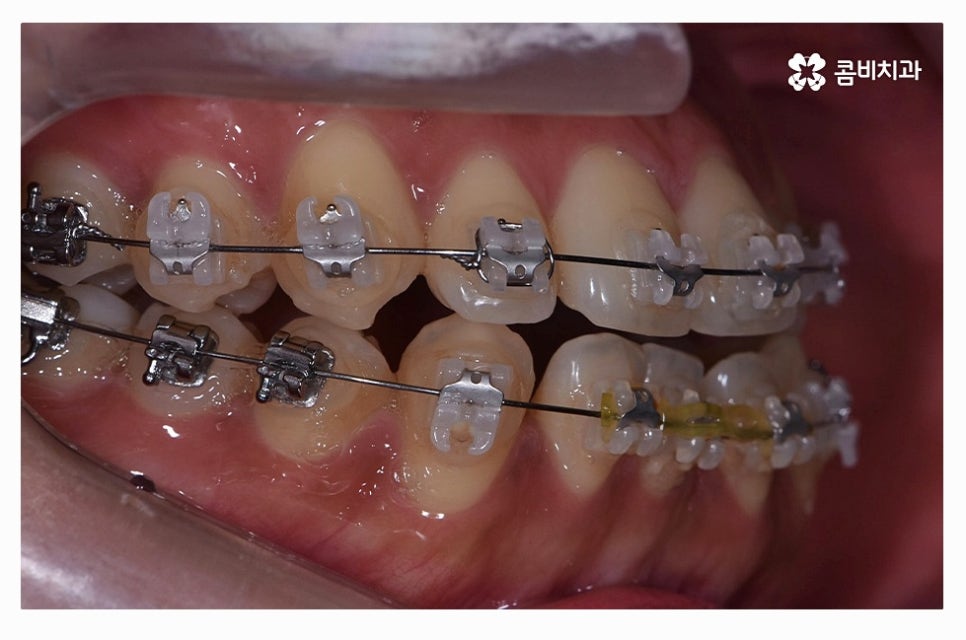

치아교정은 장기간의 치료 계획을 세워야 하기 때문에

교정 효율성이 좋고, 상대적으로 통증이 적으며 관리가 편리한

클리피씨 장치가 보편적으로 많이 활용되고 있으며

치열 상태나 환자의 니즈에 따라서 심미성이 높은 설측교정이나

투명교정이 활용되는 경우도 있어요.

치아교정 과정은 장기적인 계획뿐 아니라 주기적인 관리와

교정 장치를 풀어낸 이후에도 유지관리까지 생각해야 하기 때문에

신뢰할 수 있는 치과 선택이 중요하며 덧니 교정에 대한 풍부한 경험과

실력을 갖춘 전문의와 함께 하는 것이 중요할 수 있는데요.